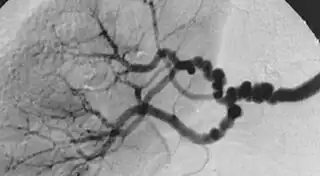

![]() Angiografía en un caso de displasia fibromuscular | ||

La displasia fibromuscular es una enfermedad poco frecuente de causa desconocida que afecta a las arterias de calibre pequeño y mediano provocando disminución de su luz y en ocasiones formación de aneurismas. Los síntomas son variables dependiendo del territorio afectado, cuando causa estenosis de la arteria renal provoca hipertensión renovascular, por el contrario si actúa sobre la arteria carótida causa accidente cerebrovascular por disminución del riego cerebral. El diagnóstico se sospecha por los síntomas y se confirma por angiotomografía computarizada, angiorresonancia magnética o angiografía, donde se observan unos vasos con estrechamientos y dilataciones alternantes según un patrón que se ha descrito como collar de perlas. El tratamiento recomendado es la angioplastia transluminal.[1][2][3]